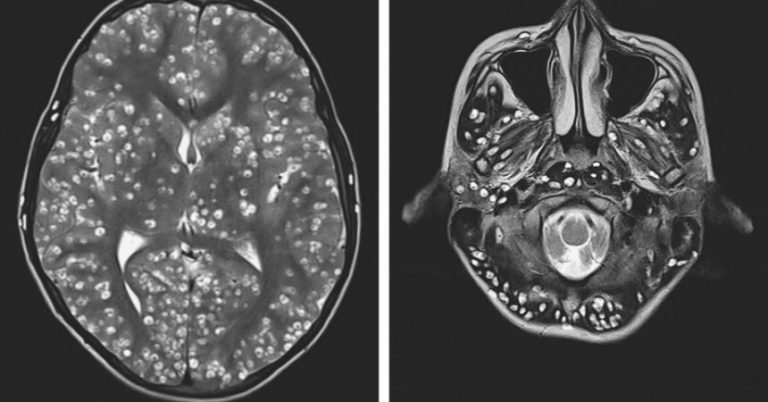

Según señala la revista New England Journal of Medicine, tras los exámenes, los médicos observaron que el paciente tenía graves lesiones quísticas en su cerebro, el cual estaba con cientos de larvas.

Para los médicos no había duda, era un caso de cisticercosis. Aunque el joven comenzó el tratamiento para revertir la situación, lamentablemente falleció a las dos semanas.